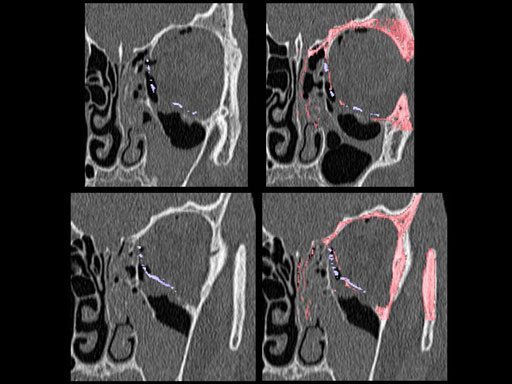

Unlike the existing two-dimensional mesh implants, the geometry of the new preformed plates will be adequate to match the individual anatomic situation of the patient in almost any case. However, the mesh parts can be individually adjusted if necessary. In these cases the solid part in the central posterior area needs to remain untouched. Areas of the orbit that do not require a bridging can be spared out by trimming the implant along the designated cutting lines in the height of the medial wall and/or length of the orbital floor area. The lateral anterior part of the plate is intentionally pre-bent higher than the orbital rim anatomy to allow free plate movement during plate positioning.

The Preformed Orbital Plates are indicated for trauma repair and reconstruction of fractures of the orbital floor, medial orbital wall or combined fractures of floor and medial wall. It should be noted that in three-wall fractures where the lateral wall is also involved, a second orbital implant, ( i. e. the mesh plate) must be used in addition to the pre-formed orbital plate.

30 year old male patient with fracture of left orbital floor and medial wall.

Provided by Dr Dr Marc C Metzger, Freiburg, Germany.